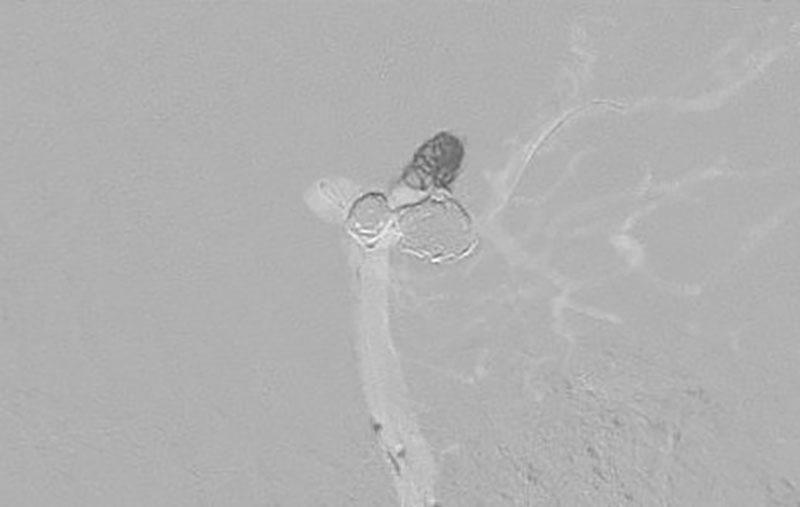

No.1600 手術前

No.1600 手術中

No.1600 手術後

'25年12月

くも膜下出血

脳底動脈瘤破裂

40代

救急外来